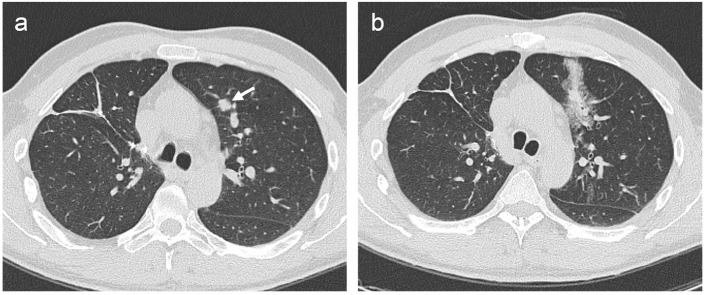

Purpose: Percutaneous biopsy has demonstrated high accuracy in diagnosis of lung nodules, but the technique is not innocuous and a yield decrease in lesions smaller than 20 mm has been reported. We carried out a prospective study to evaluate and compare the complications and efficacy of percutaneous core needle biopsy (CNB) of solitary solid lung nodules, which were performed with two types of automatic guns.

Methods: 330 consecutive CT-guided CNB were included. Tru-cut or end-cut 18G devices were used alternatively. Nodules were categorized by their size: ≤10 mm, 11-20 mm and >20 mm. Incidence of complications such as pneumothorax or hemoptysis and factors influencing them (nodule size and depth within lung parenchyma) were evaluated. Diagnostic accuracy of CNB achieved in the three groups of nodules regarding the two different needles were calculated and statistically evaluated and compared.

Results: We performed 68 CNB in nodules ≤10 mm, 130 in 11-20 mm and 132 in >20 mm. Pneumothorax appeared in 24.2% of them, but only 5.7% required drainage. Hemoptysis was developed in 9.4% and abundant hemoptysis with hypoxemia was observed in only 4.2% of patients. Regarding appearance of complications between the two needle types, no significant differences were found. A higher risk of hemoptysis was observed in nodules ≤10 mm (OR = 3.87; 95% CI = 1.24-12.06, P = 0.019) and in those located deeper in pulmonary parenchyma (OR = 2.21; 95% CI = 1.04-4.69, P = 0.038). End-cut needles reached a diagnostic accuracy of 93.7%, 92.1% and 98.3%, in nodules sized ≤10 mm, 11-20 mm and >20 mm, respectively. Corresponding results for tru-cut were 84.7%, 88.5% and 92.1%. In spite of differences reaching up to 9% in smaller nodules, intra-group results were not significant.

Conclusion: Both needles have similar complications rate. Despite not having observed statistically significant differences between the two types of needles, end-cut devices have demonstrated a higher diagnostic yield in the three groups of nodules and could be a more suitable option especially for CNB of nodules ≤10 mm.